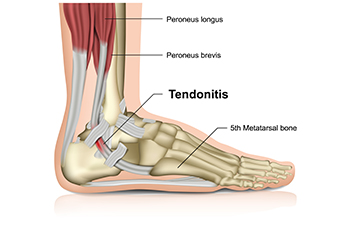

Achilles Tendonitis

Achilles tendonitis is another cause of heel pain. Similar to plantar fasciitis, inflammation of the Achilles tendon will cause heel pain due to stress fractures and muscle tearing. A lack of flexibility of the ankle and heel is an indicator of Achilles tendonitis. If left untreated, this condition can lead to plantar fasciitis and cause even more pain on your heel.

Achilles Tendonitis and How to Find Relief

Achilles tendonitis is inflammation of the tendon connecting the calf muscles to the heel bone. It is often caused by overuse, sudden increases in physical activity, or wearing unsupportive footwear. Common symptoms include heel or lower leg pain, stiffness, and swelling, especially after periods of rest or intense movement. Risk factors include having tight calf muscles, flat feet, and repetitive stress from running or jumping. A podiatrist can diagnose the condition and create a personalized treatment plan that may include stretching exercises, proper footwear, orthotics, or advanced therapies to reduce inflammation. If you have any of the above symptoms, it is strongly suggested that you promptly consult a podiatrist who can accurately diagnose and treat Achilles tendon injuries.

What Is the Achilles Tendon?

The Achilles tendon is a tendon that connects the lower leg muscles and calf to the heel of the foot. It is the strongest tendon in the human body and is essential for making movement possible. Because this tendon is such an integral part of the body, any injuries to it can create immense difficulties and should immediately be presented to a doctor.

The Causes, Types, and Treatments of Achilles Tendon Injuries

Tendons are fibrous tissues that connect muscles with bone. The Achilles tendon is the largest tendon in the body. It connects the calf muscles at the back of the leg with the heel, and facilitates movements such as jumping, running, and walking.

Because the Achilles tendon is engaged so frequently and bears a great deal of pressure and stress throughout the day, it can become injured. Achilles tendon injuries cause the tissue to become irritated, inflamed, and swollen. Pain can come on gradually or be immediate, and will vary from mild to severe depending upon the injury. Where the pain occurs will vary as well, from just above the heel up through the back of the leg. There may also be stiffness in the tendon.

Achilles tendon injuries can often be caused by repetitive stress. They may also occur while running, playing tennis, gymnastics, football, basketball, dancing, soccer, baseball or other sports that require speeding up, slowing down, or pivoting quickly. Wearing high heels, falling from an elevation, stepping in a hole, having flat feet, bone spurs, tight leg muscles or tendons, wearing improper athletic shoes, exercising on uneven surfaces, or starting a new type of exercise can also cause Achilles tendon injuries.

The two most common Achilles tendon injuries are tendonitis and ruptures. Tendonitis causes painful inflammation and can occur in different parts of the tendon. Non-insertional Achilles tendonitis occurs when the fibers in middle of the tendon begin to break down, thicken, and swell. This condition typically affects younger, more active adults. Insertional Achilles tendonitis occurs where the tendon inserts into the heel bone. It is common for bone spurs to form with this type of injury. This condition can affect people of any age and level of activity.

Achilles tendon ruptures are a tear in the tendon. These breaks may be partial or complete. There may be an audible popping noise at the moment of injury and the pain will be sudden and severe.

An Achilles tendon injury can be diagnosed by your podiatrist after they examine you, check your range of motion, and possibly perform a calf squeeze test or review an X-ray or MRI. Depending on the type and severity of your injury, your podiatrist may treat your condition with rest/ice/compression/elevation (RICE), nonsteroidal anti-inflammatory medications, heel lifts, and stretching and strengthening exercises. If you have torn your Achilles tendon, treatment may include physical therapy, ultrasound, shockwave therapy, or possibly even surgery.